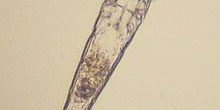

Comment se fait le diagnostic ?

Il se fait généralement très facilement par un simple raclage de la peau. Ce raclage doit être profond (le vétérinaire peut faire légèrement saigner à l’endroit du prélèvement) pour pouvoir atteindre le parasite qui se loge dans les follicules pileux (à la base du poil). Ce prélèvement s’effectue sans anesthésie.

Dans certaines races à la peau épaisse (sharpei, bouledogues…), des biopsies de peau sont parfois nécessaires.